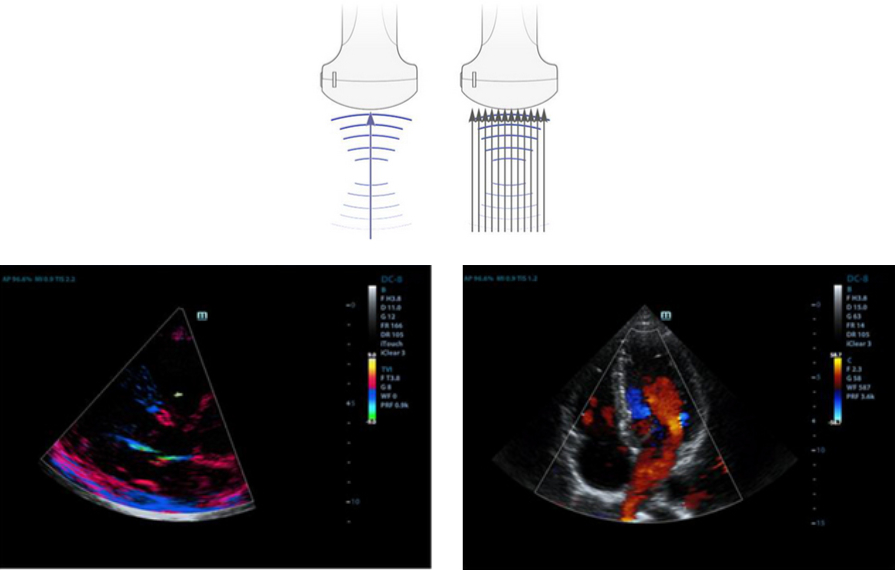

Formowanie wi?zki wzmocnionego echa

Formowanie wi?zki wzmocnionego echa pozwala na wykorzystanie standardowo ignorowanych sygna?├│w echa z przyleg?ych wi?zek do stworzenia wyra?niejszej i silniejszej wi?zki obrazowania, zapewniaj?cej lepsz? rozdzielczo?? ?nieostregoŌĆØ obrazu i g??bsz? penetracj? obrazu.

Tworzenie wielu wi?zek - Multi-Beam

Mo?liwo?? tworzenia maksymalnie 12-krotnego strumienia dla jednej przesy?anej wi?zki, co zapewnia doskona?? rozdzielczo?? czasow? i wy?sz? cz?stotliwo?? od?wie?ania obrazu.